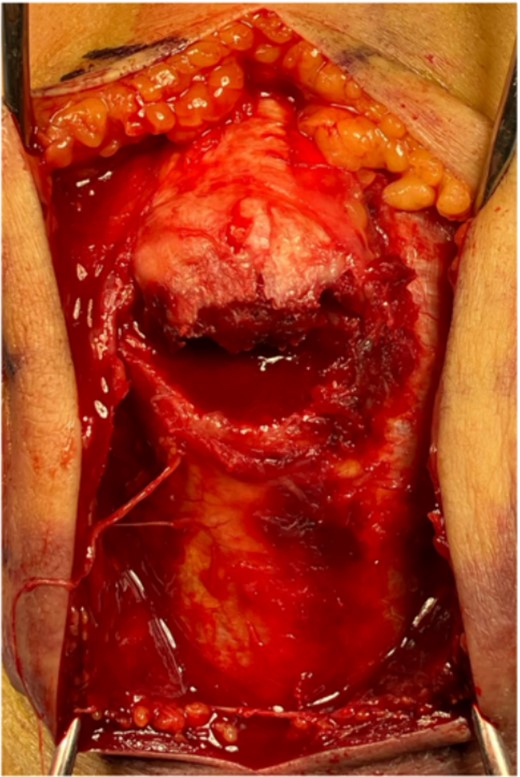

The surgery was performed in the left lateral recumbent position. An incision was made in the posterior midline over the right olecranon. Triceps brachii tendon rupture was not observed (Fig. 2). The fracture fragment was inverted, and two 1.4-mm JuggerKnot® All-Suture Anchors (Zimmer Biomet, USA) were inserted into the ulna proximal to the fracture site without perforation into the elbow joint. Subsequently, sutures were threaded through the triceps brachii muscle; the dislocated bone fragment was pulled together with the triceps brachii muscle. Despite maintaining the elbow at a 30° flexion position, two Quattro® Link Knotless anchors (Zimmer Biomet, USA) were inserted into the ulna distal to the fracture site to reduce and fix the fragment using the suture bridge procedure (Fig. 3). However, upon flexing the elbow joint to 90°, the bone fragment was displaced and anchors were loose. Therefore, we opted to use the McLaughlin cerclage technique, utilizing a 2.3-mm BroadBand® Tape (Zimmer Biomet, USA) passing through a predrilled hole perpendicular to the ulnar shaft. The suture was crossed over the posterior aspect of the ulna and tightened in a figure-of-eight manner through the triceps brachii tendon (Fig. 4). This procedure resulted in no dislocation of the fracture site, even when the elbow joint was flexed to 130°.

(A) The suture bridge technique is performed using JuggerKnot® All-Suture Anchors and Quattro® Link Knotless anchors. A schematic of the surgical field is shown in (B) frontal and (C) lateral views. Proximal anchors are JuggerKnot® All-Suture Anchors, while distal anchors are Quattro® Link Knotless anchors.